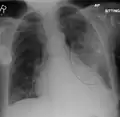

Normal AP CXR

Normal lateral CXR

AP CXR showing left lower lobe pneumonia associated with a small left sided pleural effusion

AP CXR showing right lower lobe pneumonia

AP CXR showing pneumonia of the lingula of the left lung

Right upper lobe pneumonia as marked by the circle.

Left upper lobe pneumonia with a small pleural effusion.

Right lower lobe pneumonia as seen on a lateral CXR